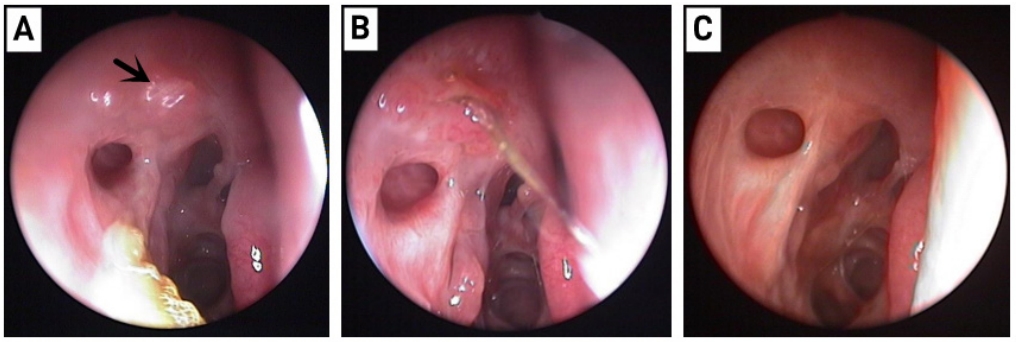

手术方法:术中沿中鼻甲前缘附着点上方约8 mm处做弧形切口,形成一约1 cm × 1.2 cm黏膜瓣,钝性分离至泪颌缝,以泪颌缝为标志,用美敦力(Medtronic,美国)IPC刨削动力系统粗磨,咬除上颌骨颈突,造一直径为1 cm大小的骨孔,暴露泪囊,经上泪小点置入探针,撑起泪囊壁,近上缘弧形切开泪囊内侧壁,形成一黏膜瓣,开放前组筛窦,剪开鼻黏膜瓣,使其贴附于泪囊造口周边骨面上,泪囊瓣与鼻黏膜瓣之间无需缝合,周围填充沾有妥布霉素地塞米松眼膏眼药膏的吸收性明胶海绵[14],见瘘口形成良好,检查无出血。合并泪总管、泪小管狭窄时植入泪道引流管,分别自上下泪小点插入引流管,自鼻腔内勾出并打结。术中同期处理鼻腔、鼻窦病变。手术均由同一位经验丰富技术熟练的医师完成。术后随访及处理:术后1个月内用药为布地奈德鼻喷雾剂2次/天,0.1%氟米龙滴眼液滴术眼3次/天。术后每2周复查1次鼻内镜检查,复查3次后根据恢复情况确定随访间隔时间,所有患者随访时间均大于6个月。随访内容包括以下3项:1)鼻内镜下鼻腔处理,清除鼻腔内血痂、分泌物、黏膜粘连及增生的肉芽组织,如发现肉芽组织增生(图1、3),则用枪镊夹除肉芽组织,造瘘口周围涂妥布霉素地塞米松眼膏,其中物理清除联合TA组予鼻黏膜下注射TA注射液(40 mg/mL)0.3 ~ 0.5 mL,保证注射面积覆盖80%肉芽组织创面(图2、4),间隔2周复查,如发现肉芽复发则再次清除并注射TA。2)泪道冲洗,分别经上下泪小点以地塞米松注射液和生理盐水冲洗泪道。3)如术中联合植入泪道引流管,一般于3个月后拔除。

图2 造瘘口肉芽组织增生处理后

Figure 2 After ostium granuloma was excised

图3 合并插管患者造瘘口肉芽组织增生

Figure 3 Ostium granuloma in patient with silicone intubation

图4 清除肉芽后局部注射曲安奈德

Figure 4 Intralesional triamcinolone injections after removed the ostium granuloma